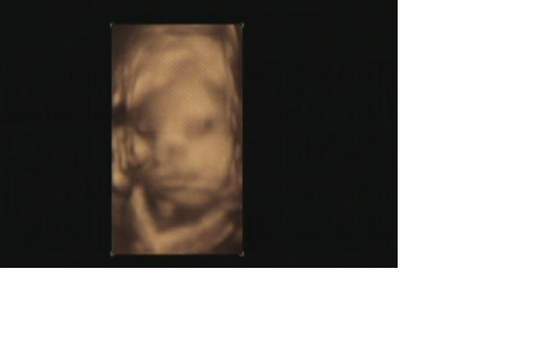

i gratulacje dla rodzicow!!!faktycznie sie synus wbil rowniutko w czasie ;-)